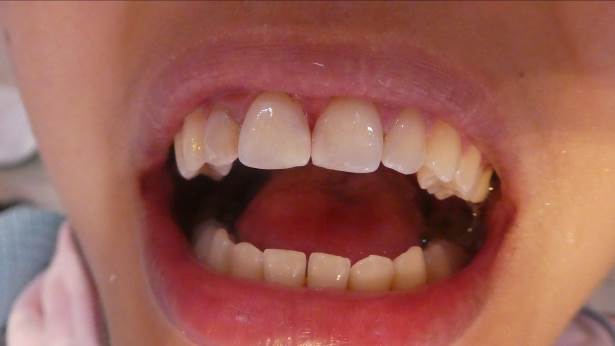

Carl S. and Friedrich K. came to us from August 11th to September 22nd. Both had studied dentistry in Ulm and now wanted to help the patients here at the clinic with their dental problems. Having worked together before, they quickly settled in. From the first day, the dental clinic was full. During their stay, an Apex device, which is needed for root canal treatment, arrived, and we ordered the digital X-ray machine mentioned in the last letter. This was a real benefit for the young dentists and was used quickly and frequently. Because it is digital, it offers the advantages of filmless image display, and we don't need X-ray films or developing solutions for this device. The initial investment was somewhat higher, but in the long run, there are many advantages. The young dentists also performed the first root canal treatment, so the Apex device was used immediately. Like the dentists before them, they also noticed the poor condition of the patients' teeth, which motivated them to work even more diligently and efficiently. They also trained the patients in good oral hygiene.

On October 8th, a new team of dentists arrived so that dental treatments could continue. Harun S., Alice F., Katharina G., and Anna H. They had studied dentistry at the University of Regensburg and now wanted to work full-time. Unfortunately, holidays and the local elections reduced the number of patients significantly. Alice F. had to leave after a few days because she became ill. More patients could have been treated, but for the population, their teeth were not a priority in October, unfortunately, because the need is still great.

In November, we moved our old dental unit to the elementary school so students could have regular checkups with our visiting dentists. We will also be conducting the fluoride prophylaxis program there in the future and will then schedule children who need treatment at the dental clinic. This "outpost" will bring many benefits, and we are pleased that the old dental chair is still being put to such good use. We want to thank the German Dental Aid Organization for its many years of support for our dental clinic.